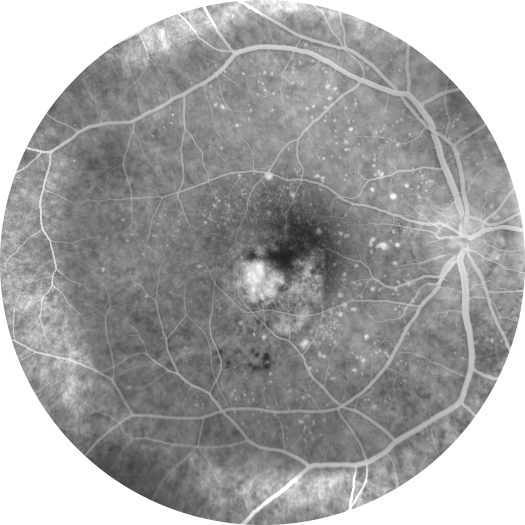

Adölesan Stargardt Hastalığınd ...

Adölesan Stargardt Hastalığında İlk Başarılı Faz 3 Çalışma: Tinlarebant ile Reti ...